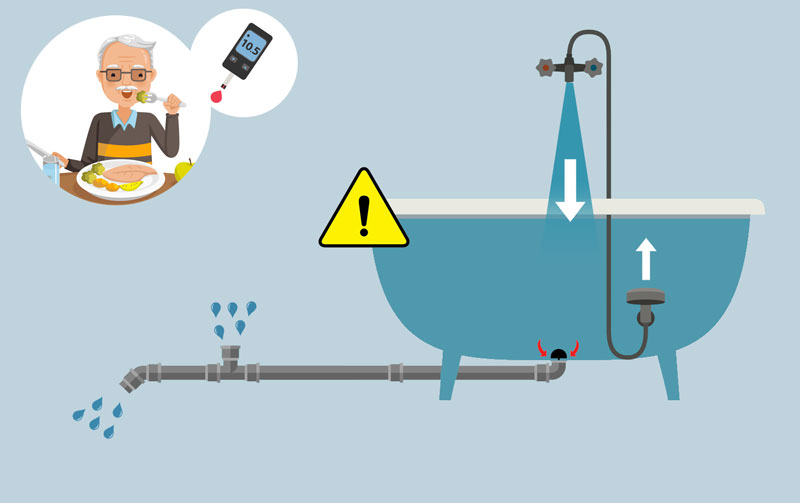

Et la berbérine dans tout ça ? La berbérine agit à 3 niveaux dans cette situation.

1) Elle facilite d’abord le soulèvement du bouchon de la baignoire, en augmentant la sécrétion d’insuline et son efficacité (3).

Cette sécrétion d’insuline supplémentaire va contribuer à faire entrer plus facilement les sucres excédentaires dans les cellules, et donc à diminuer le "niveau de la baignoire". Mais l’insuline ne sert pas seulement à ça : elle contribue à inhiber tout un tas de processus métaboliques qui aggravent le diabète de type 2 et l’insulinorésistance...

2) Elle met, ensuite, en place un système de siphon dans les canalisations pour « aspirer » l’eau en trop dans la baignoire et accélérer le flux d’évacuation.

En termes scientifiques, on dit qu’elle stimule la glycolyse, un processus de dégradation du glucose pour produire de l’énergie. En améliorant l’utilisation des sucres par les cellules, elle permet d’accélérer la dégradation des sucres et donc de décharger plus rapidement les vaisseaux sanguins.

3) Et, dernier point, elle contribue à réduire le flux du pommeau de douche qui remplit la baignoire par le bas (5-6).

En fait, elle ralentit la synthèse du glucose dans le foie à partir de composés non-glucidiques (ce qu’on appelle la néoglucogénèse et qui est très problématique chez les personnes diabétiques) (7).

En attendant, le résultat de ces 3 mécanismes est implacable : le niveau de la baignoire diminue, et ça se traduit inévitablement dans les analyses des personnes diabétiques.